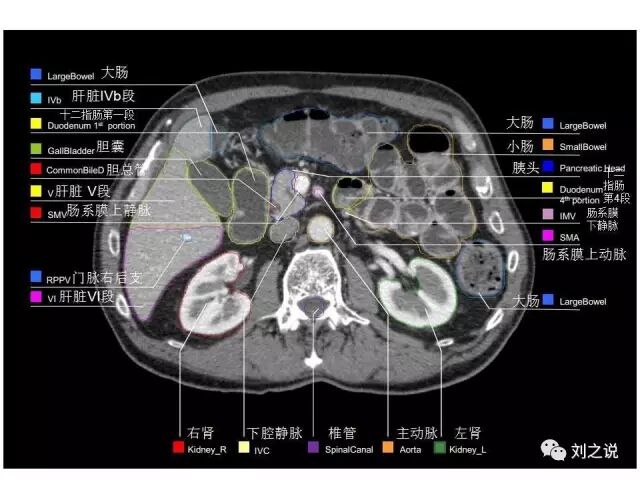

参考RTOG共识和3D-body解剖。

来源:刘之说